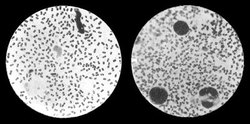

Zhruba o dva měsíce později, dne 11. srpna, třetí účastník historie (v této záležitosti okrajový), britský důstojník zdravotní služby lékař Lawson, který byl také k epidemii přivelen, zveřejnil o nálezu zprávu v Lancetu, což byl a dodnes je špičkový anglický lékařský časopis. Sdělení doprovázely čtyři obrázky. O týden později byla pak v Lancetu o nálezu otištěna zpráva samotného Kitasata. Je však z ní prý zjevné, že její autor měl o svém nálezu pochybnosti. Nebyl ani schopen říci, zda je jeho bacil gramnegativní, či grampozitivní. Psal, že u něho pozoroval pomalý pohyb a tentokrát nezaznamenal jeho růst na želatině. Snad si nebyl jist, nemá-li před sebou ne jeden, ale více smíšených druhů mikrobů. Sdělení má působit dojmem spěchu jakoby ve snaze nebýt v objevu předběhnut. (Tyto Kitasatovy práce z Lancetu se mi přes veškerou snahu nepodařilo sehnat. Znám je jen „z druhé ruky“, i když nepochybně seriózní.)

O Yersinově nálezu poprvé referoval ředitel pařížského Pasteurova ústavu Duclaux dne 30. července na zasedání francouzské akademie věd. V září pak Yersin publikoval v Annales de l'Institut Pasteur důkladnou, několikastránkovou a ilustrovanou práci, ze které je zřejmé, že v jeho případě jde nepochybně a jednoznačně o nález „morového bacila“.